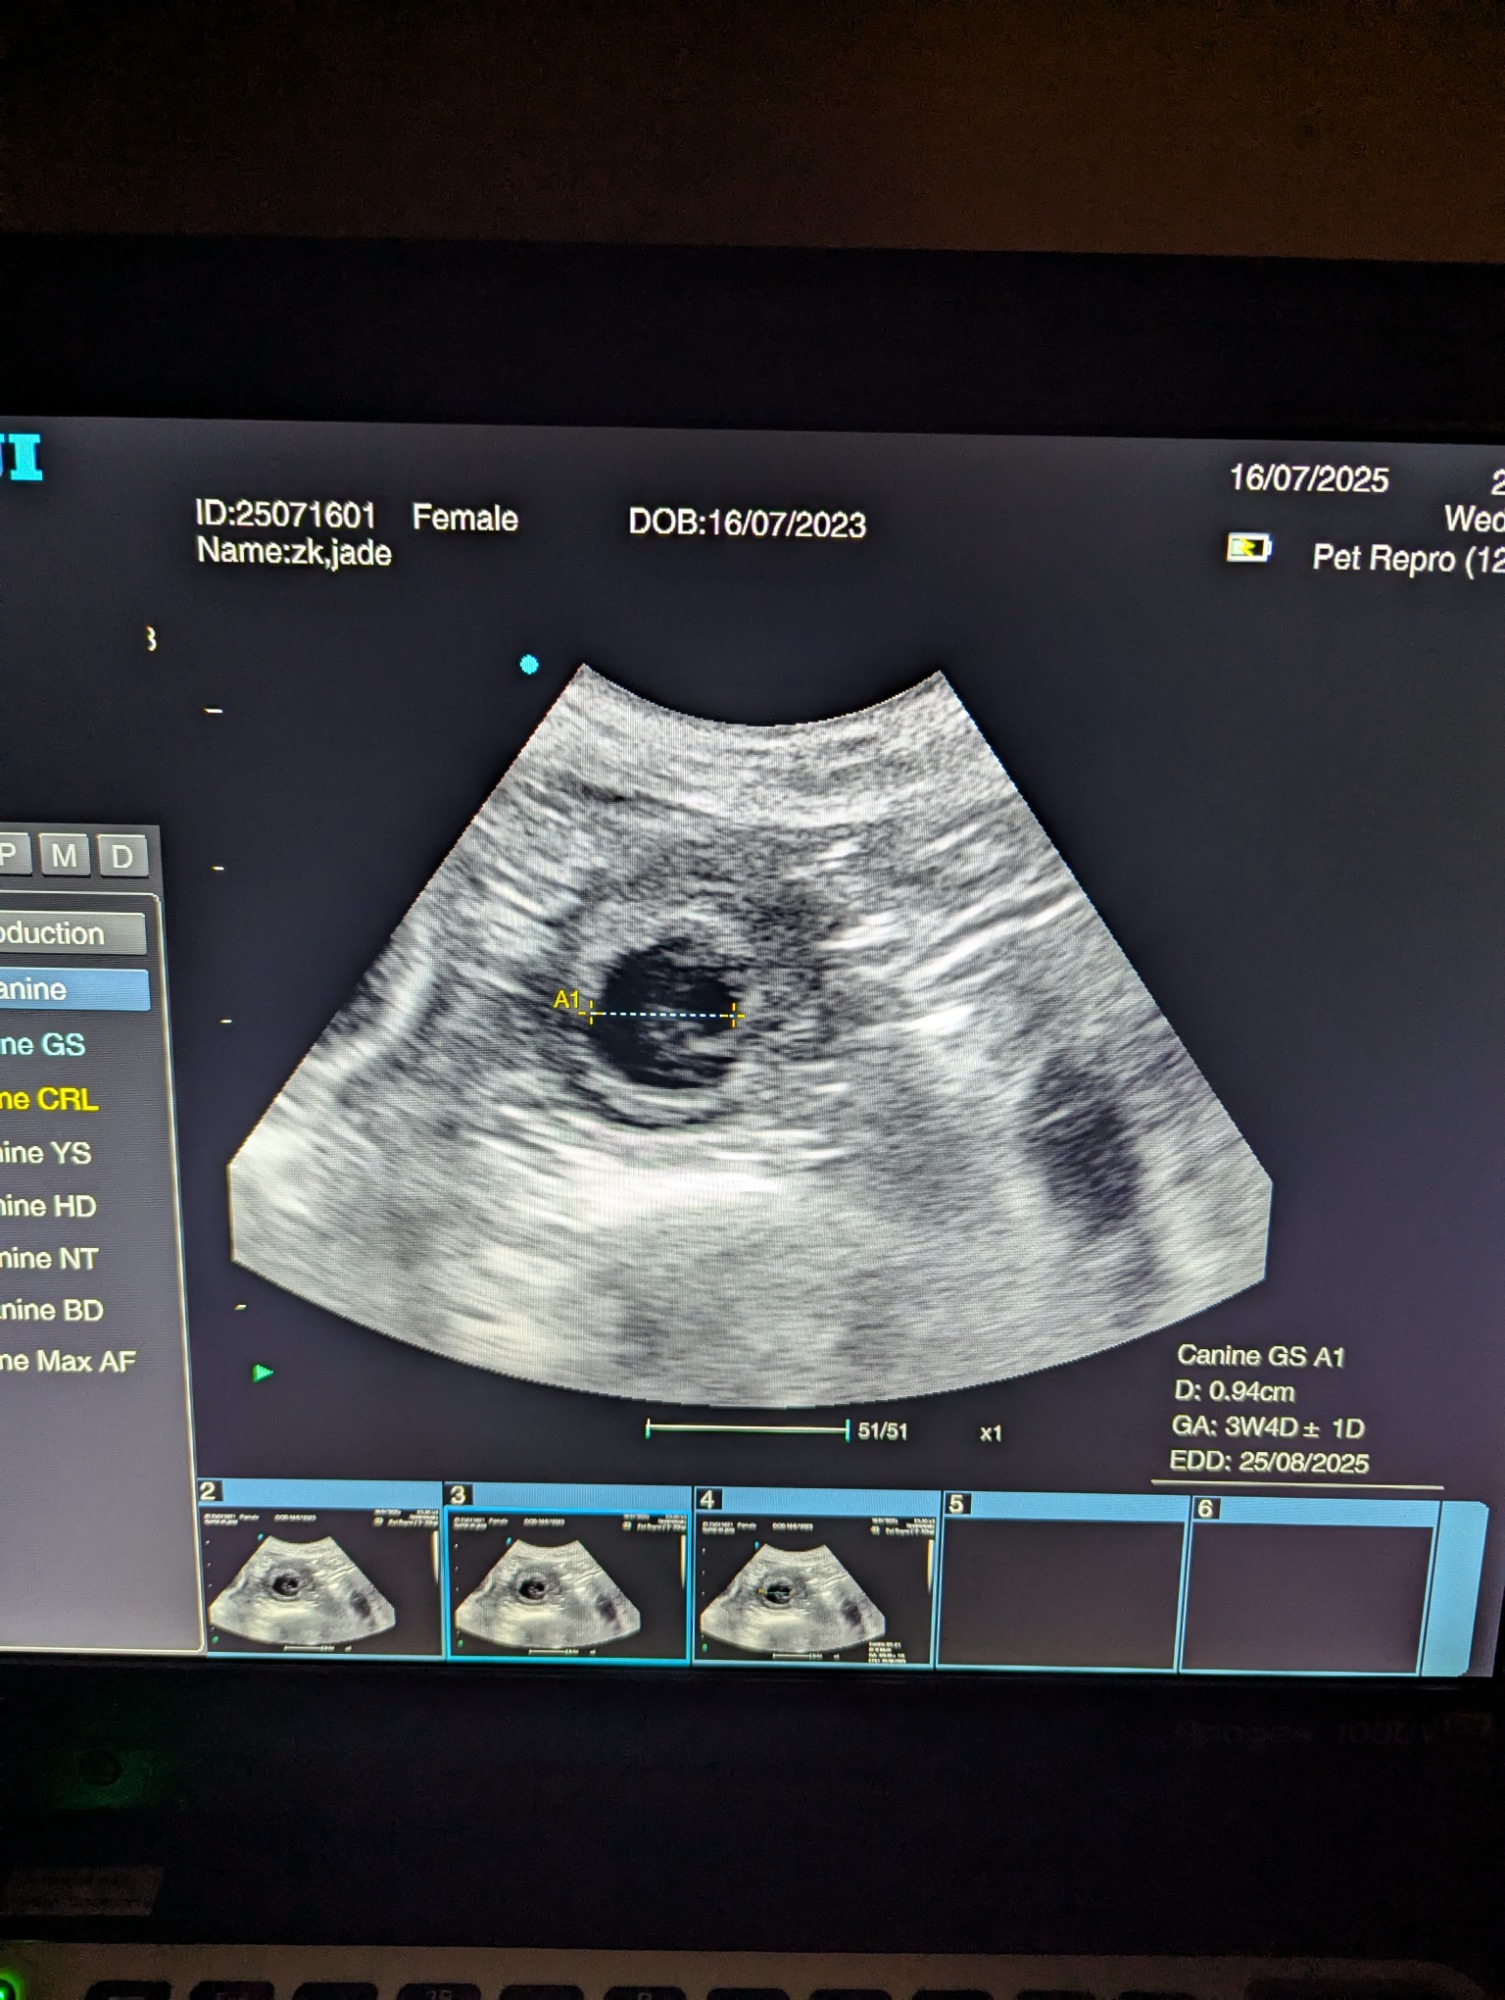

Ultrasound pregnancy scanning is a safe, non-invasive way to confirm pregnancy in dogs and cats, offering breeders and pet owners peace of mind and vital information to support responsible care. It allows us to detect gestational sacs, assess foetal development, and estimate litter size—all while ensuring the wellbeing of the animal.

Pregnancy can sometimes be detected as early as Day 18 post-mating, but scanning at this stage is not routinely recommended. Embryos are still developing and may not be clearly visible, and there is a natural risk of embryo resorption, which can lead to misleading or inconclusive results.

For the most accurate and reliable scan, we advise booking between Day 25 and Day 32, when pregnancy is more easily confirmed and foetal structures are clearer. If an early scan is performed and no pregnancy is detected, we offer a FREE complimentary re-scan after 7 days at the clinic to ensure clarity and support informed decision-making.

Our approach balances early insight with ethical care—always prioritizing the comfort of the animal and the accuracy of the results.